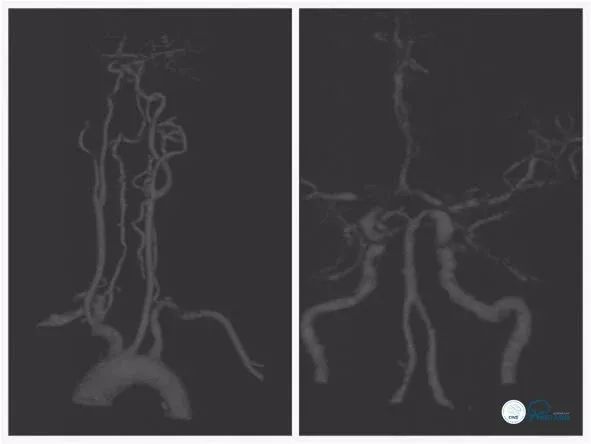

头颅MRA:右颈内动脉颅内段狭窄(图2)。

图2